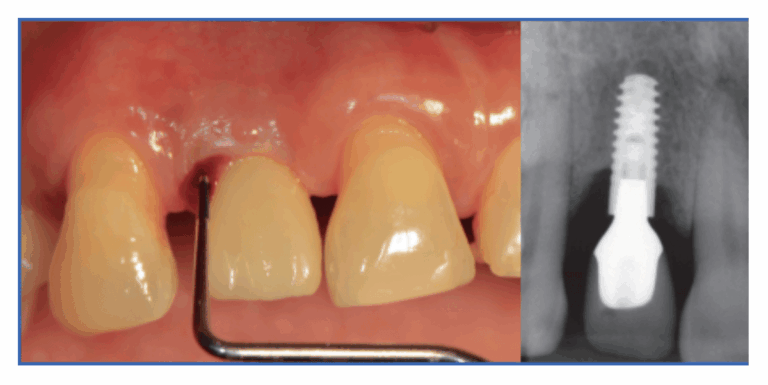

La periimplantitis es una infección que afecta a los tejidos que rodean un implante dental y provoca pérdida de hueso. Es la “enfermedad de las

En Facialia (Silla, Valencia) vemos con frecuencia la encía retraída después de un implante. Nuestro objetivo es claro: diagnosticar la causa y ofrecer la solución